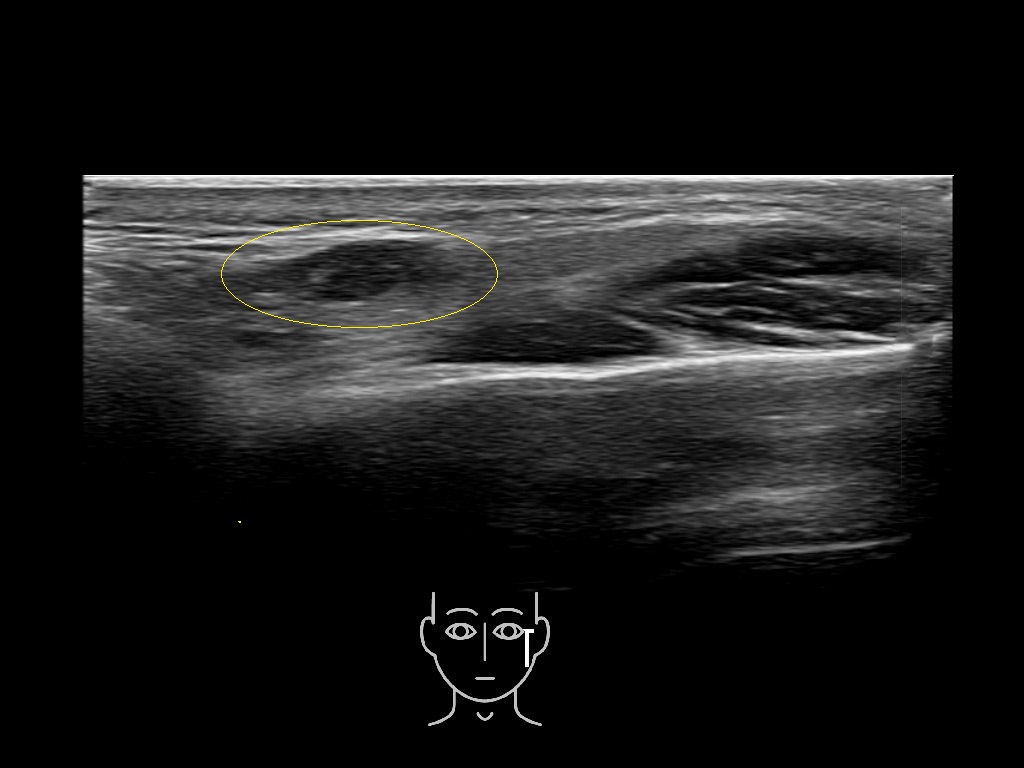

Parotid

Filler injections in the parotid gland may go unnoticed, however, inflammatory reactions and abscesses may occur. Hypervascularity can be seen with color doppler. Filler deposits are supposed to be injected into the superficial fatty layer . The space to inject into this layer may be limited. Routinely we measure a width of 2-4 millimeters with sometimes subcutaneous layers being less than one millimeter thick.

Study the first image to recognize the different layers. If you are sure about the layers, swipe to the second image to view the answer (if applicable).